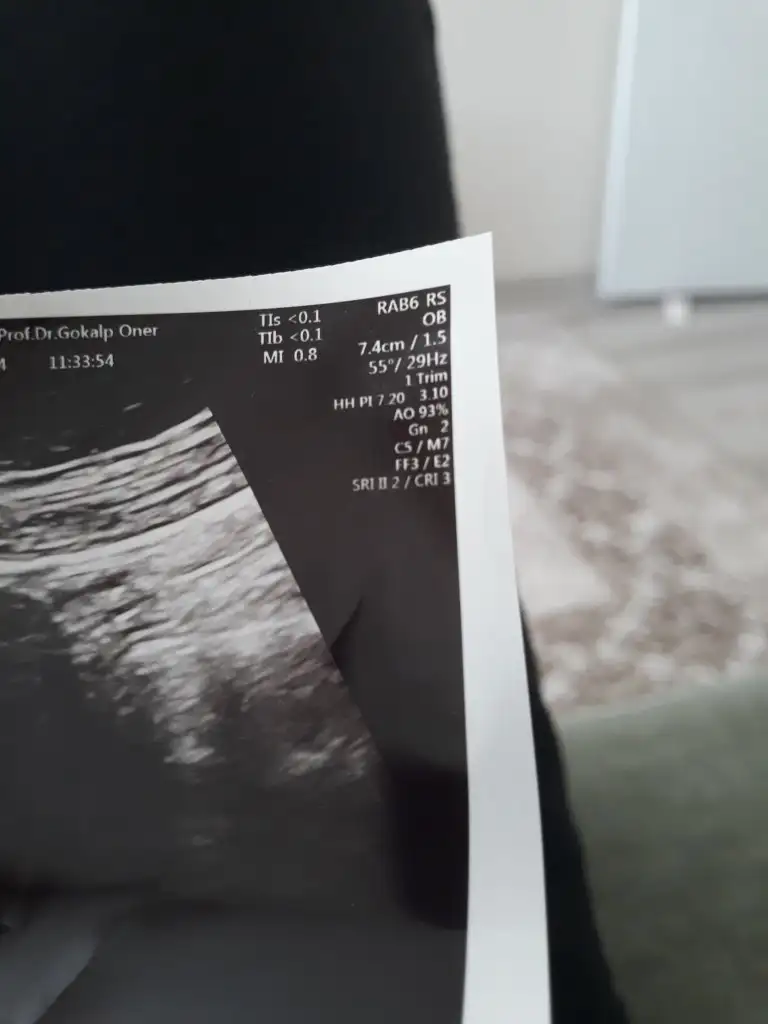

Dediğiniz değer burdan hangisi acabaKüçük bence inşallah duyarsın ben cuma günü duydum crl 0.72 cm di pek anlamıyorum ama küçük olduğu için duyulmamış olabilir

En alt sağ köşede yazıyor CRL olanDediğiniz değer burdan hangisi acaba

Benimkinde yazmiyo maalesefEn alt sağ köşede yazıyor CRL olan

Kese ultrasonuysa benim dediğim değer yazmaz bebek boyutu buDediğiniz değer burdan hangisi acaba

Kese ultrasonu o zaman canım yazmaz kesedeBenimkinde yazmiyo maalesef